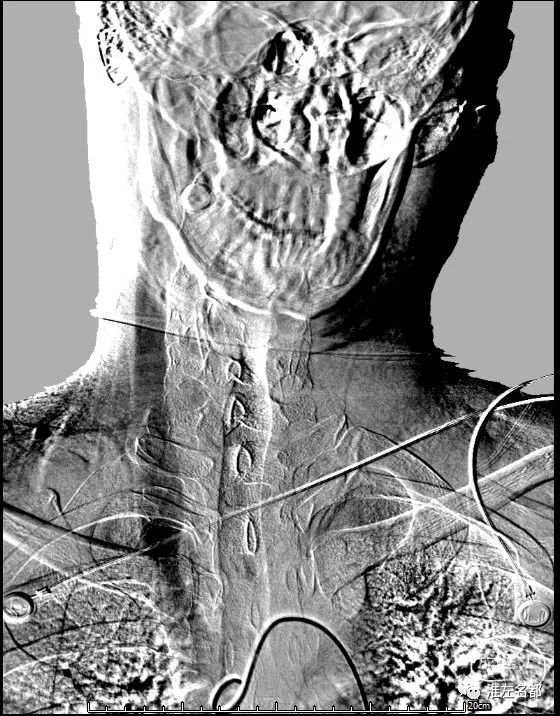

此为特发性颅高压横窦狭窄患者,

优势右侧横窦伴局部管腔狭窄,

上图是术前DSA,

术后是支架植入后DSA,

投射角度是左侧斜位+汤氏位。